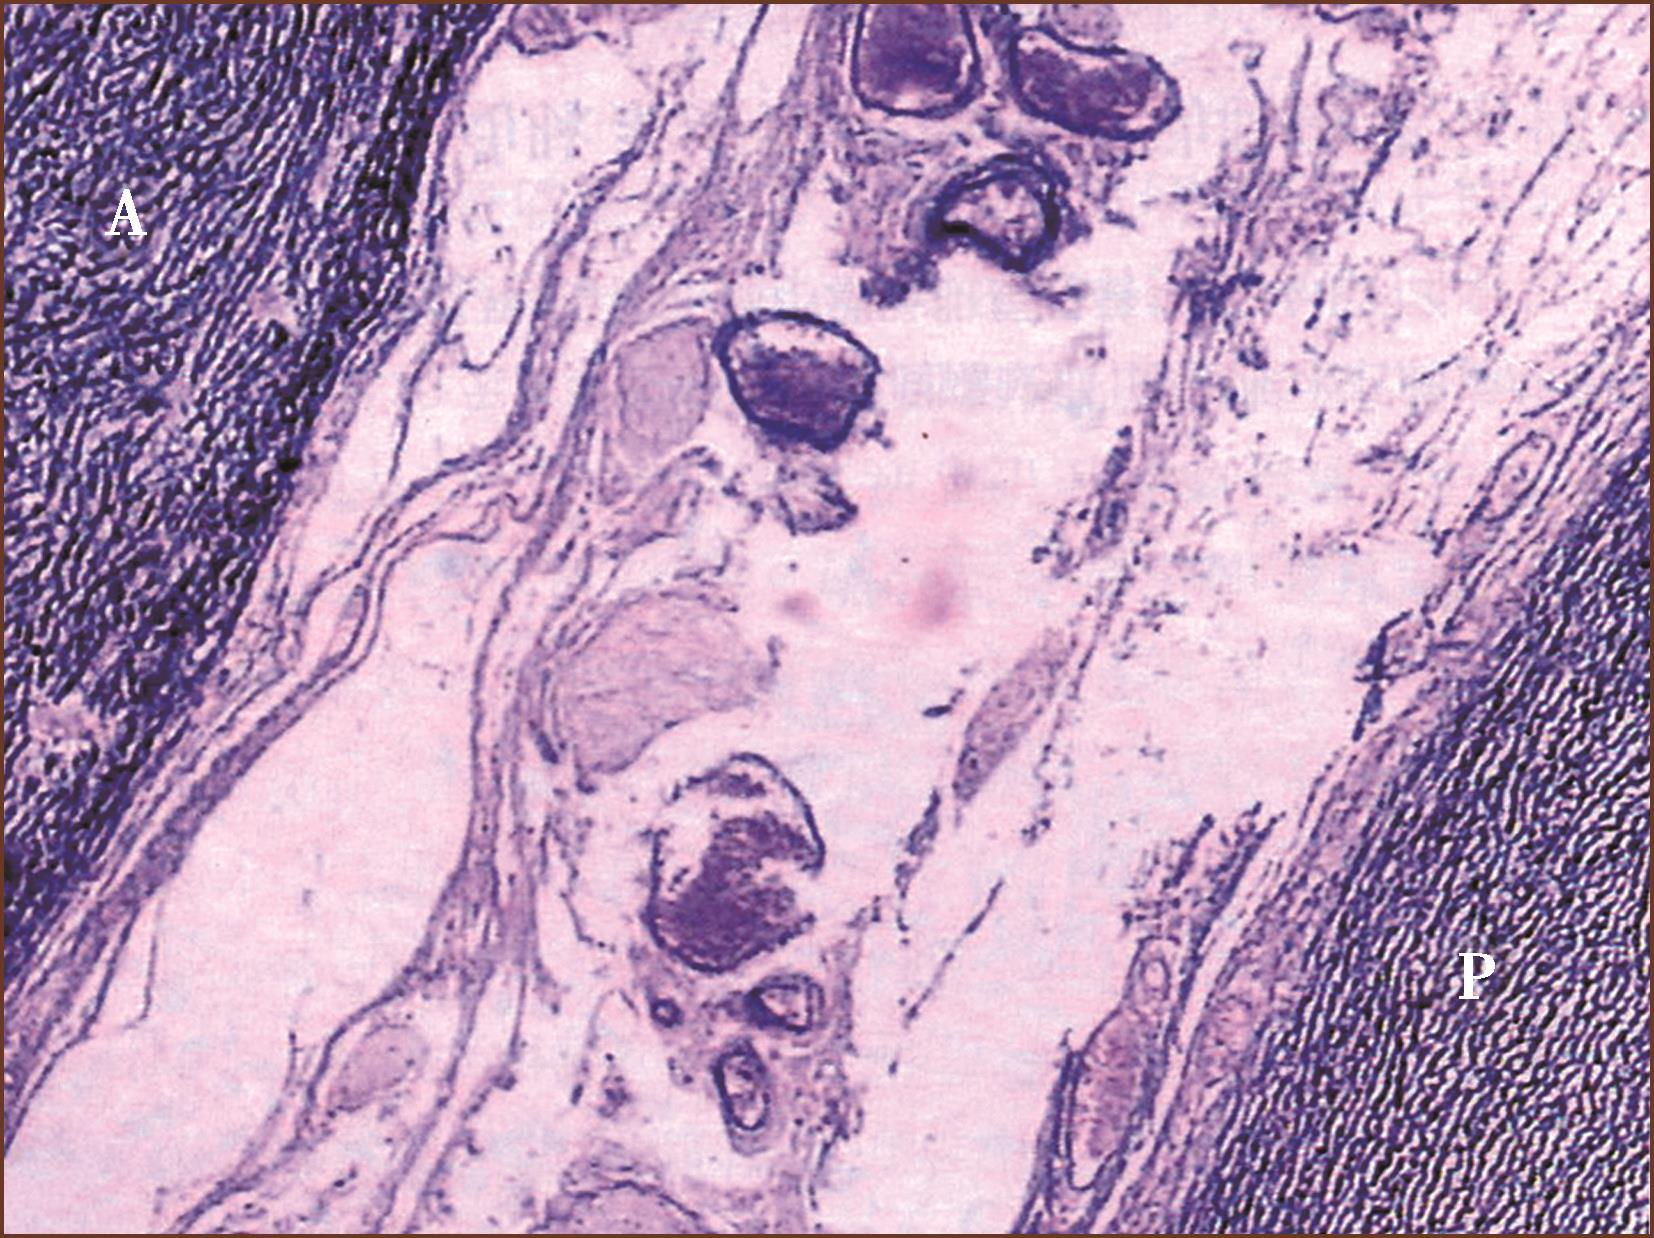

图1-3-10 正常胎儿升主动脉(A)、肺动脉干(P),具有相似的丰富的弹力纤维板(ET+VG染色,低倍放大)